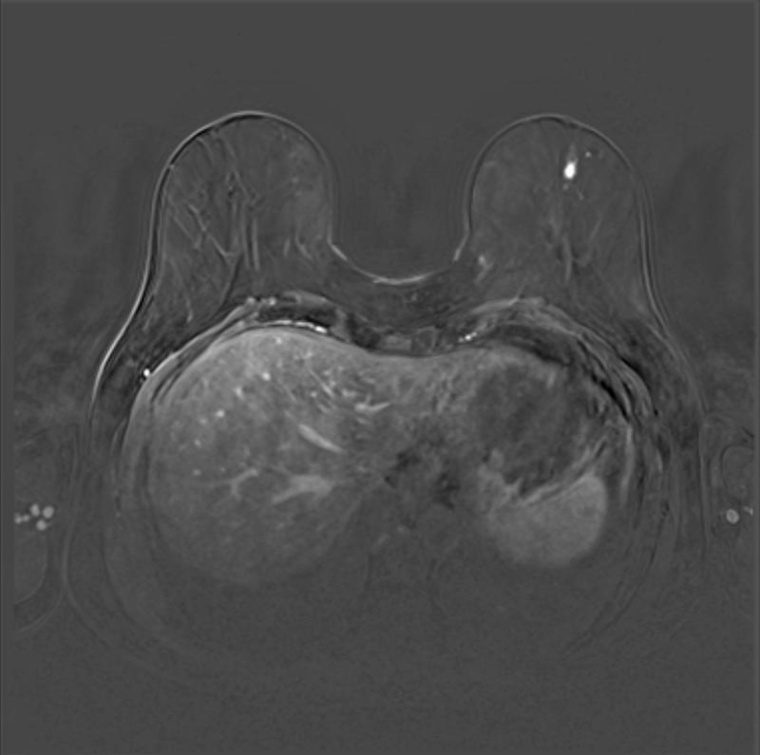

Was beinhaltet die Mammadiagnostik? Die Ultraschalluntersuchung, auch Mammasonographie genannt, ist sehr breit verfügbar und vor allem bei dichtem Brustgewebe hilfreich. Die Mammographie hingegen ist nur in der Radiologie möglich. „Bei der Röntgenuntersuchung sehen wir Mikroverkalkungen, die wir sonst mit keiner anderen bildgebenden Modalität sehen“ erklärt Stephanie Sauer. In solchen Mikroverkalkungen können klassische Krebsvorstufen, ein so genanntes DCIS, stecken. Seit vielen Jahren gibt es im Brustzentrum ein Mammographiegerät mit integrierter Tomosynthesefunktion und seit letztem Jahr nun auch eine sehr gute Datenlage zum Einsatz der Tomosynthese in der Früherkennung. „Damit erhalten wir einen quasi 3D-Blick auf die Brust, was vor allem bei dichtem Brustgewebe hilfreich ist“, so Stephanie Sauer. Das dritte bildgebende Verfahren in der Mammadiagnostik ist die Magnetresonanztomographie (MRT). Dabei handelt es sich um eine funktionelle Bildgebung. „Ein Tumor der schnell wächst, hat einen hohen Energiebedarf und wird besonders gut durchblutet. Entsprechend gut nimmt er das Kontrastmittel auf, das wir dann auf den Bildern sehen“, erläutert Stephanie Sauer die Vorteile. Das MRT-Verfahren ist zur präoperativen Planung, aber speziell auch für Hochrisikopatientinnen nützlich, denen aufgrund einer familiären Häufung an Brustkrebserkrankungen oder besonderen Krebssubtypen ein intensiviertes Früherkennungsprogramm empfohlen wird. „Da man hier am allerschnellsten am allermeisten findet, erhalten diese Patientinnen bereits ab dem Alter von 25 oder 30 Jahren im jährlichen Rhythmus eine MR-Untersuchung“, so Stephanie Sauer, deren Forschungsschwerpunkt in einem Spezialbereich der MRT, der diffusionsgewichteten Bildgebung (DWI) liegt.